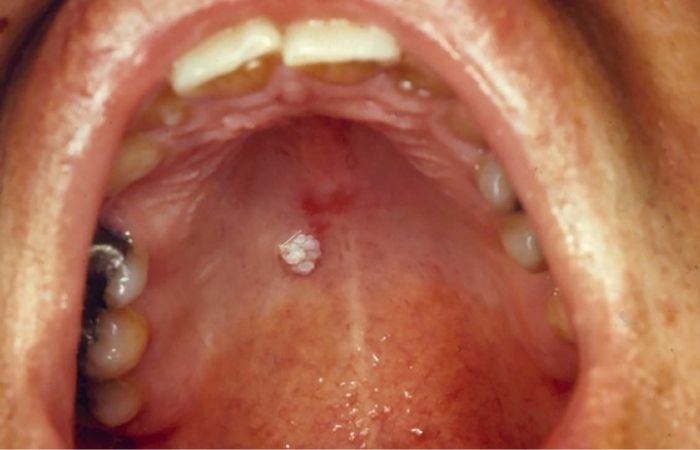

Some strains of HPV persist and can lead to major health issues, but the majority of infections go away on their own. Anus, penis, and throat cancers are known to be caused by high-risk strains of HPV, such as HPV-16 and HPV-18. Genital warts, which are not cancerous but can be upsetting, can be caused by low-risk strains.

Although HPV comes in over 100 varieties, not all of them are equally dangerous. Most cases of genital warts are caused by low-risk HPV types, such as HPV-6 and HPV-11. Despite not being cancerous, these warts can cause emotional and physical discomfort. Male cancers, such as anal, penile, and throat cancers, are most frequently associated with high-risk HPV types, such as HPV-16 and HPV-18.